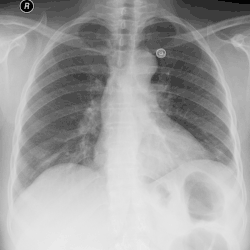

Pleural effusion

A pleural effusion is an accumulation of fluid inside the pleural space. If this collection of fluid gets large enough, it can also push structures in the chest away from it and cause a mediastinal shift. However, a pleural effusion can also pull the mediastinal structure towards itself. If this is the case, then there is an underlying condition causing the collapse of the lung on that side. An example is a tumor obstructing a bronchus and causing lung collapse and pleural effusion.[3]